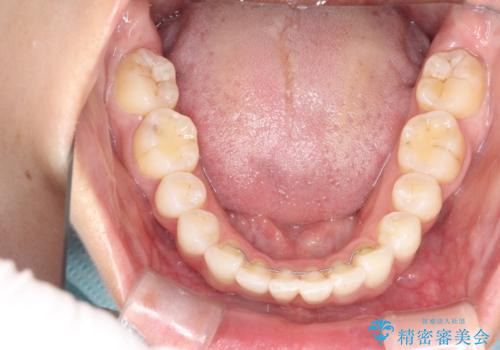

右下1が歯肉退縮していたため、アーチを拡げないように歯と歯の間を削って隙間をあけて並べています。